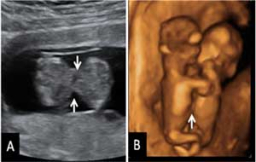

Hoy, por las técnicas de FIV, el número de gemelos o mellizos, o incluso trillizos, que nacen ha aumentado. Los embarazos múltiples, es decir cuando dentro del útero materno crecen dos o más bebés, tienen sus propias peculiaridades. Descubre cómo tienes que cuidarte en estos casos, los controles médicos que deberás seguir y comprueba con las ecografías cómo se desarrollan los bebés.